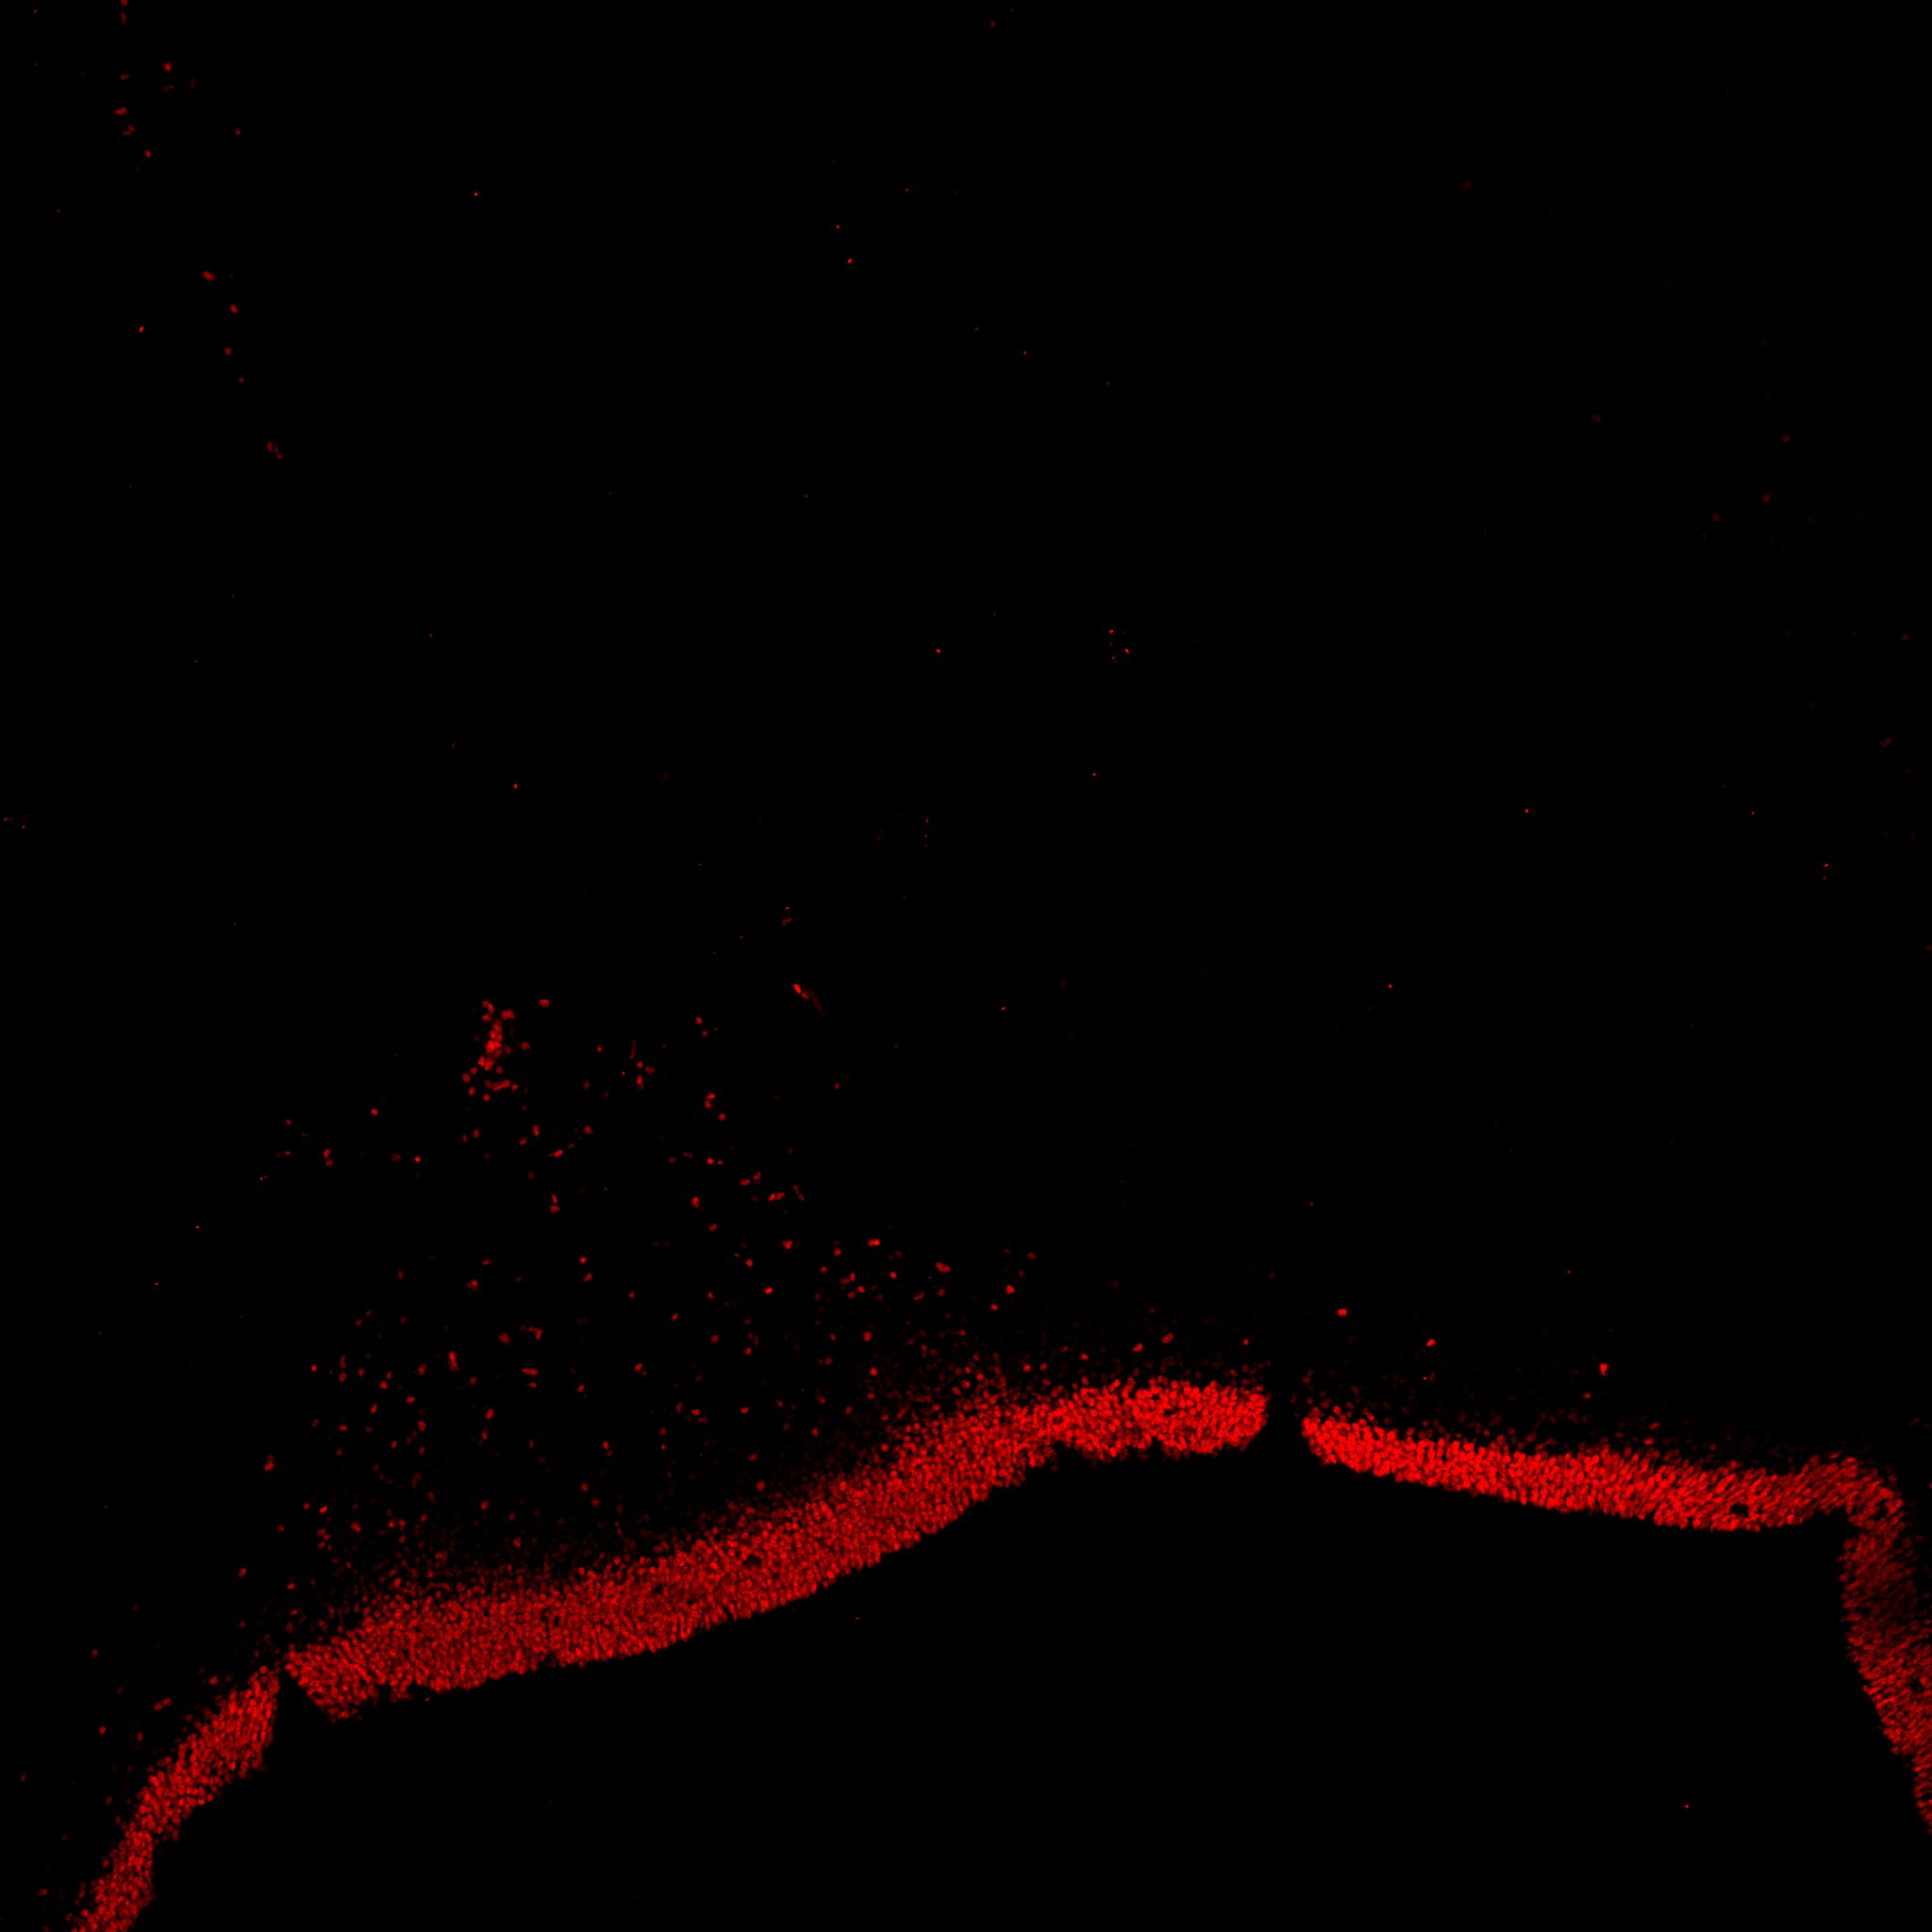

An anatomical analysis of the developing human midbrain from 6 post-conceptional weeks (PCW) to 22 PCW reveals increased tissue complexity, characterized by the emergence of dopaminergic nuclei, as highlighted by immunofluorescence analysis for tyrosine hydroxylase (TH).

TH

6PCW human midbrain